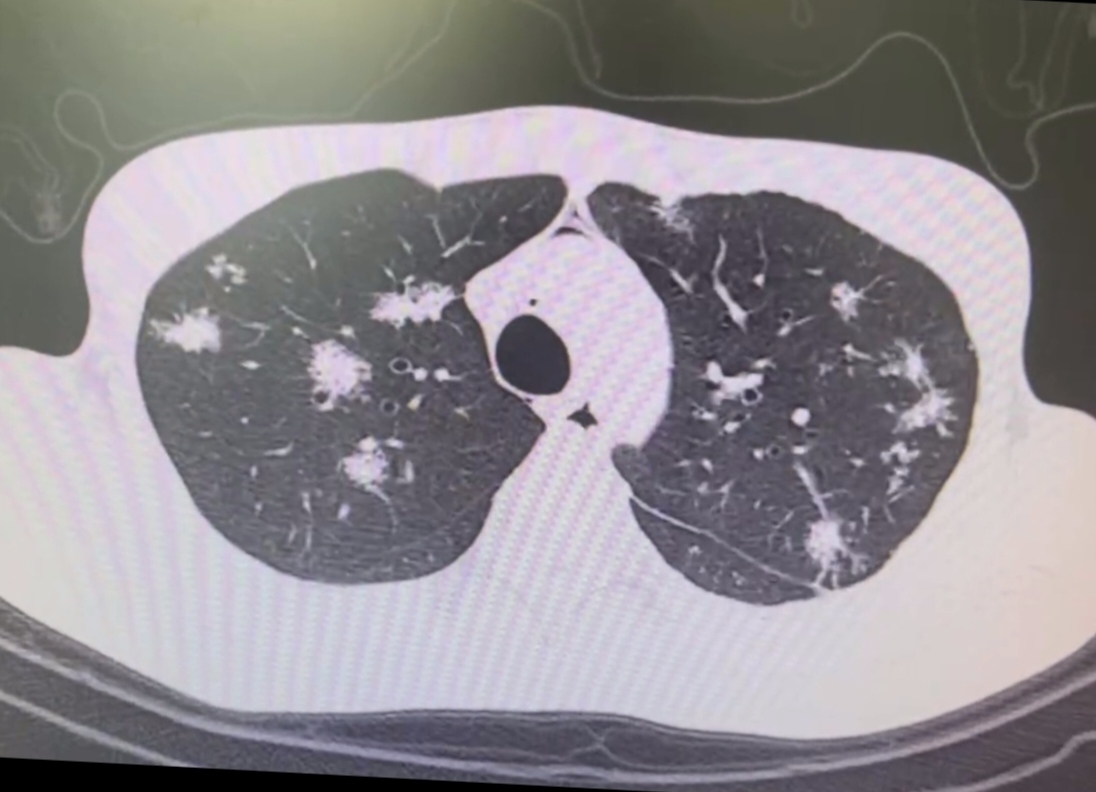

形狀暴露“真身”

如果結節形狀不規則,邊緣有毛刺、棘突,或者有分葉,又或者胸膜有凹陷,這就好比妖怪露出了它奇形怪狀的真身。在《西游記》中,妖怪現原形時往往都是張牙舞爪的。這樣的結節很可能是高危結節,存在惡性的風險,就像那化作人形卻藏不住尾巴的“狐妖”。

密度不均有“貓膩”

結節密度不均勻,內部有空泡或者血管聚集、支氣管影,這就好比妖怪的洞穴里藏著各種神秘的法寶和機關。這樣的結節可能是高危結節,存在惡變的風險,就像那隱藏著重重陷阱的“盤絲洞”。